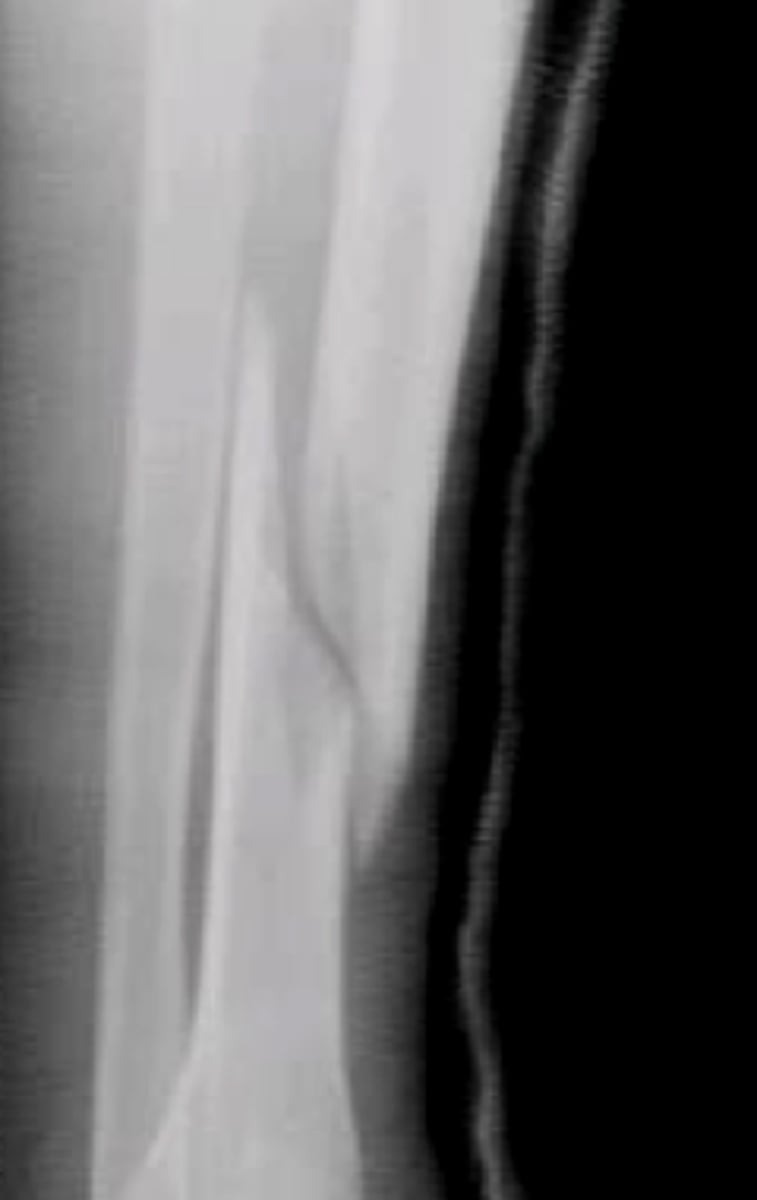

oblique fracture line

fracture occurs diagonal across bone axis

spiral fracture line

torsional fracture that spirals around bone, often due to twisting